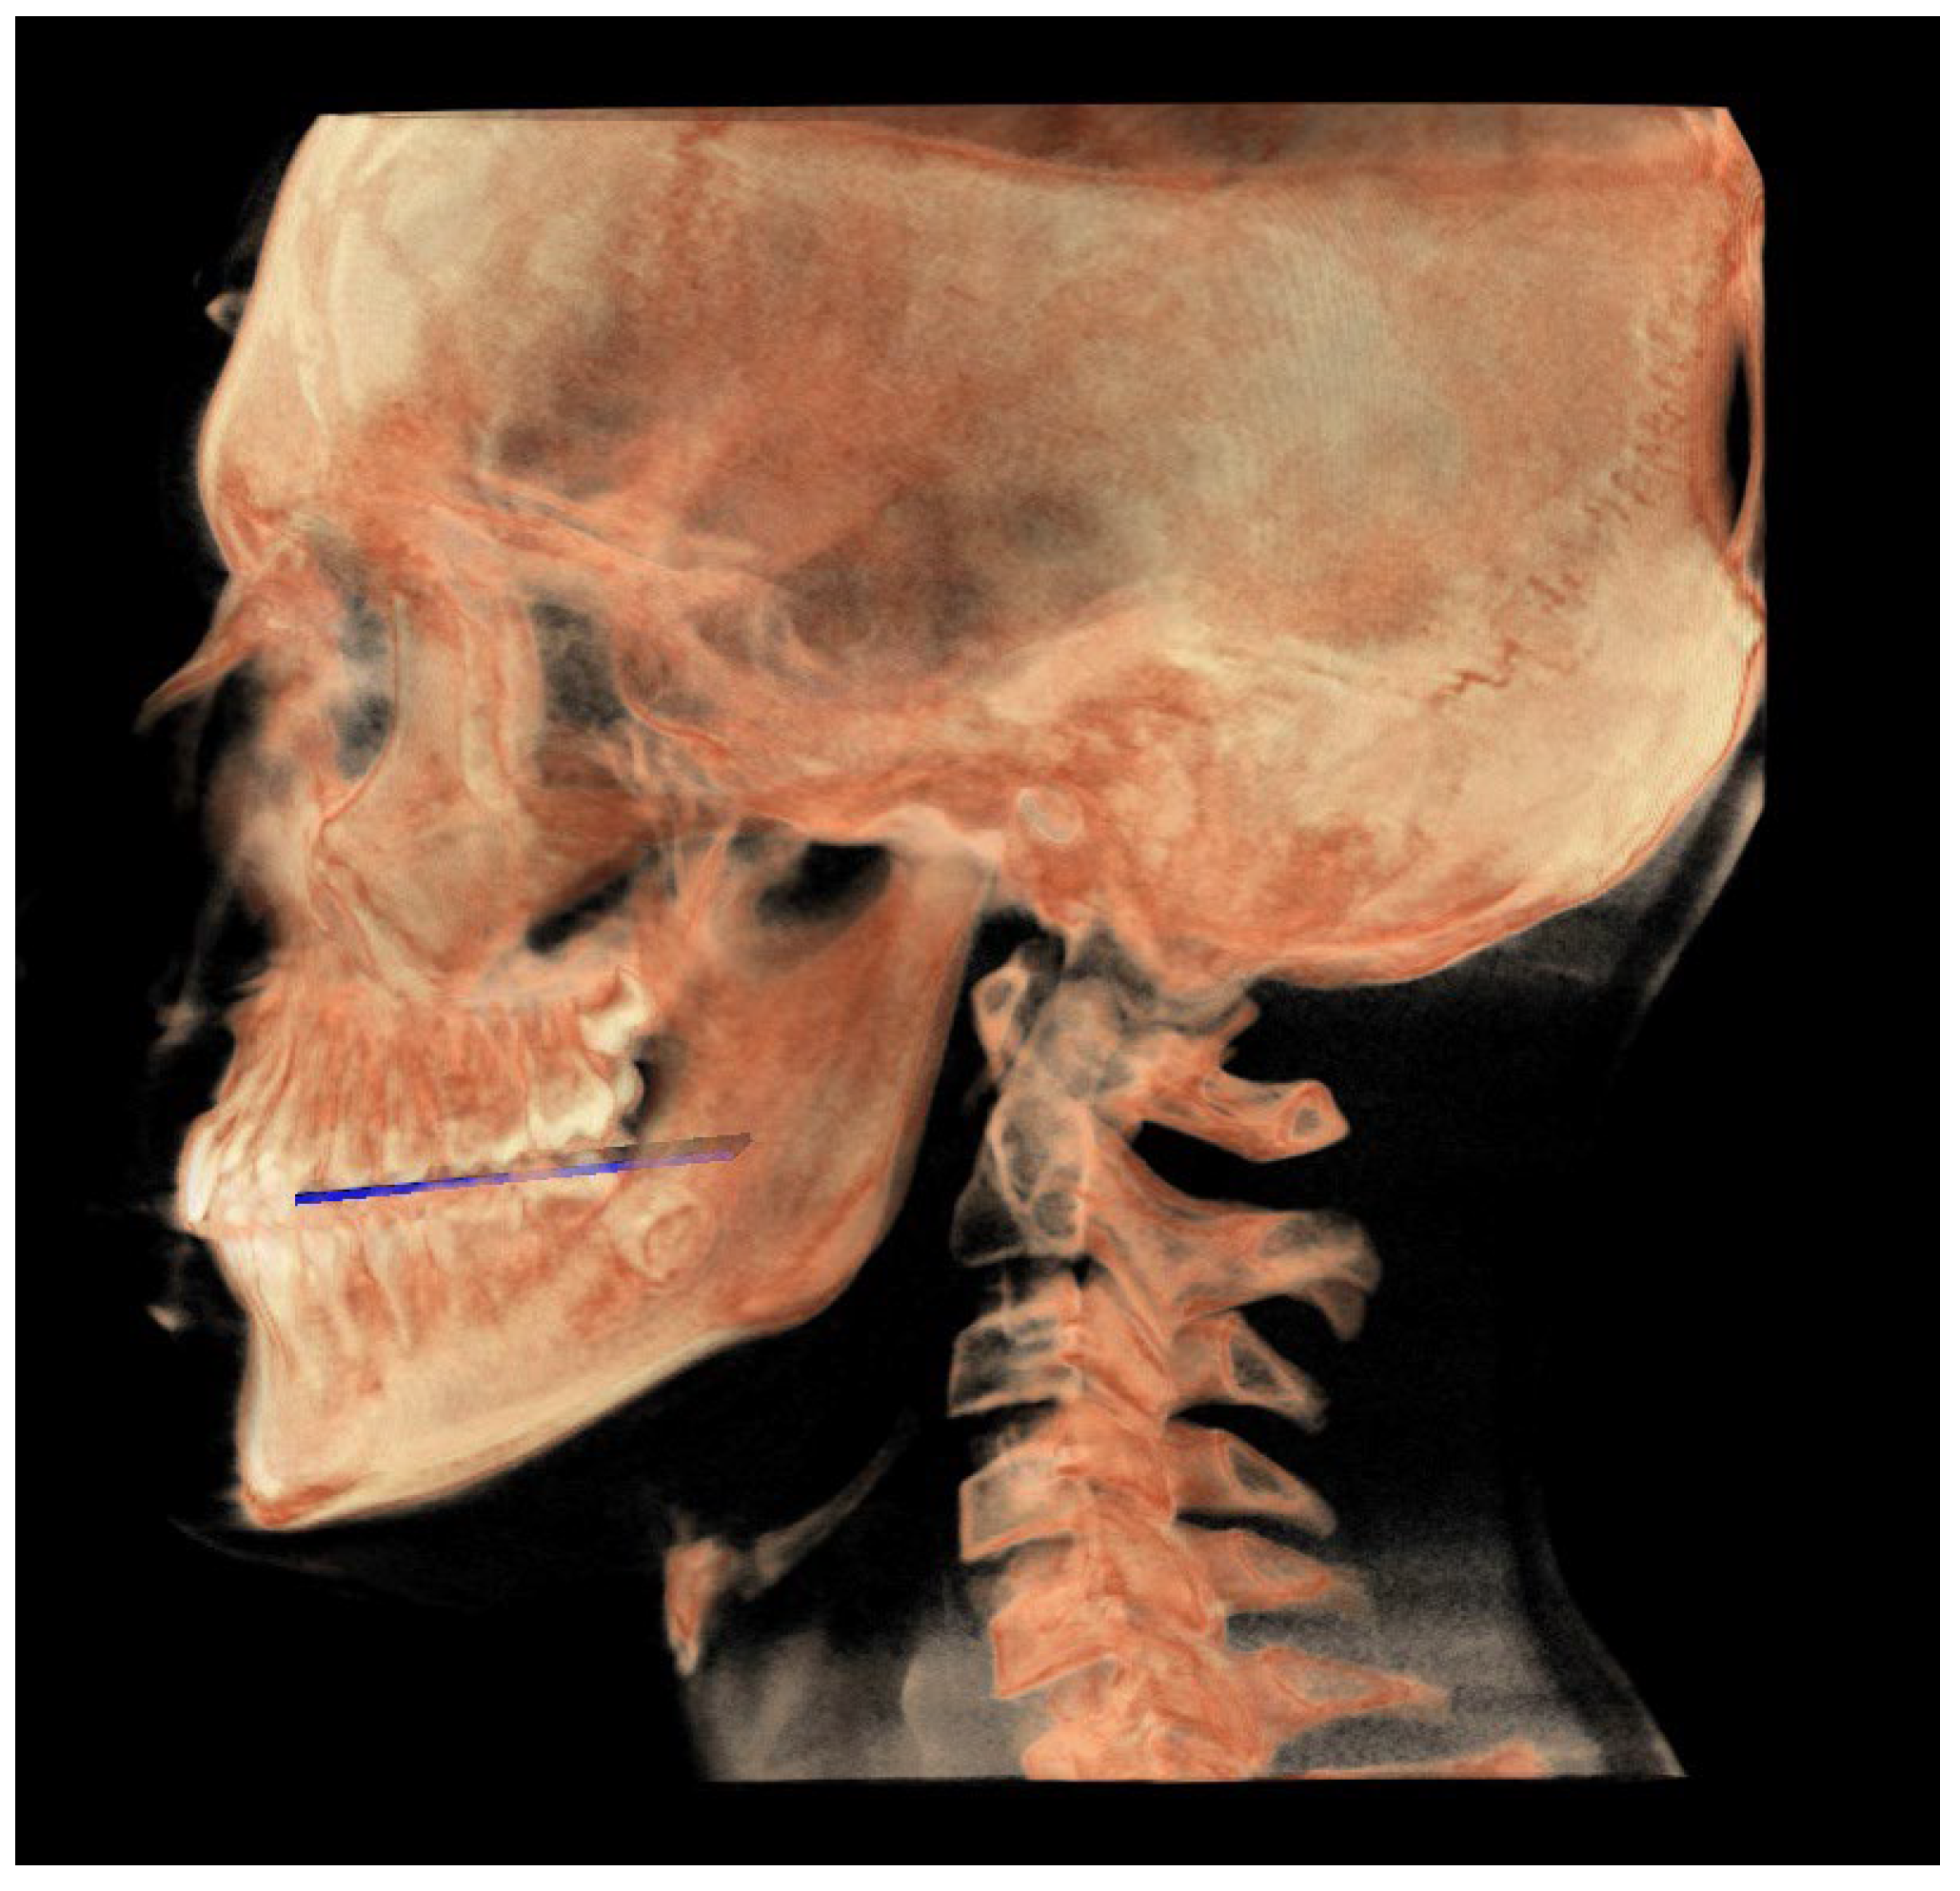

The following image shows a comparison between the neutral (blue) and individual (white) tracks (Figure 17).

Figure 17. All the planes of the individual track (white) and neutral track (blue).